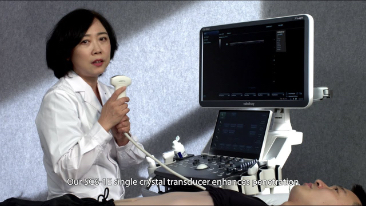

????? ??? ??? ??? ?? ?? ???? ????, ?????? ??? ?? ???? ?? ??? ??? ??? ??? ?? ???? ?? ???? ????? ???.

?? ?? ?? ??? ?? ?? ?? ???? ?? ???? OBG ?????? ?????. ?? ??, ?????(CNS) ??? ?? ?? ??? ?? ? ?????. ???? ?? ??? ?? ??? ??? ??? ?? MSP? 2D ????? ?? ???? ?????. ??? ?? ?? ? ??? ??? ???? ?? ???? ? ????.